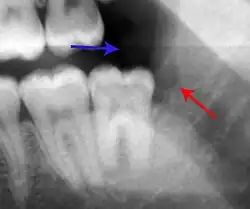

Decay (green) with apical abscess (blue) Decay (green) with apical abscess (blue)

The periodontal ligament becomes inflamed and there may be pain when biting or tapping on the tooth. On an X-ray, bone resorption appears as a radiolucent area around the end of the root, although this does not manifest immediately.[10]: 228 Acute apical periodontitis is characterized by well-localized, spontaneous, persistent, moderate to severe pain.[6]: 125–135 The alveolar process may be tender to palpation over the roots. The tooth may be raised in the socket and feel more prominent than the adjacent teeth.[6]: 125–135

- Radiographs utilized to find dental caries and bone loss laterally or at the apex.